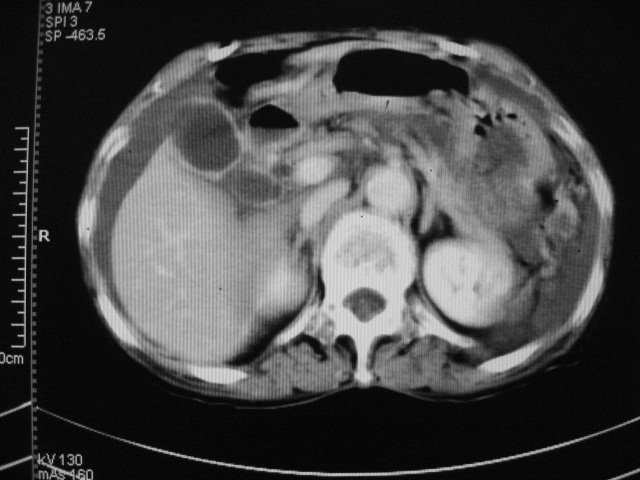

以下是引用默契在2007-9-20 17:29:00的发言:[br][br] [br] 考虑:1、胆囊占位性病变(以癌可能性大);[br] 2、中量腹水。 [br] [br]

以下是引用快乐男生在2007-9-20 15:32:00的发言:[br]图像质量不好:[br]胆囊增大,囊壁增厚,[br]可见结节突出囊腔内,[br]增强后与囊壁相仿.[br]考虑多为胆囊慢性炎症伴有胆囊体部的息肉